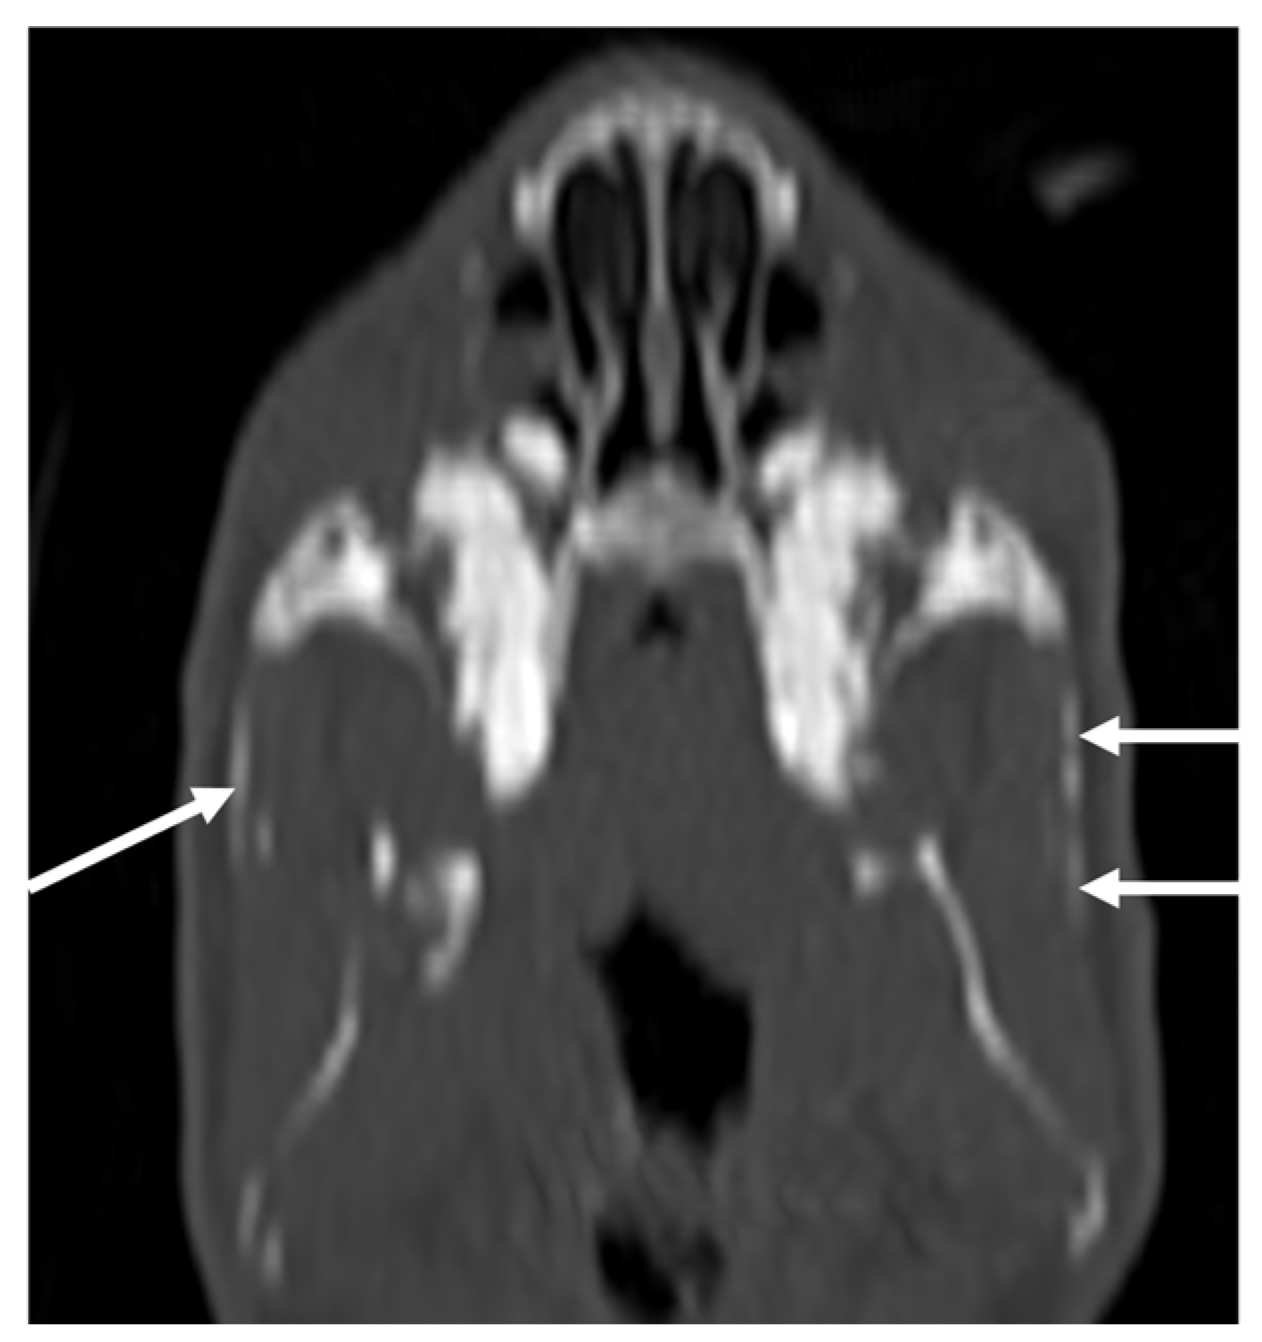

3.2. Guinea Pigs

| Eye | Exophthalmos (1/0) | Deformation (0/0) | Lens luxation (0/0) | Others: mineralization (0/26) |

| Soft tissues | Diffuse swelling (1/1) | Solid space occupying lesion (0/0) | Cavernous space occupying lesion (0/1) | Mineralization (11/0) |